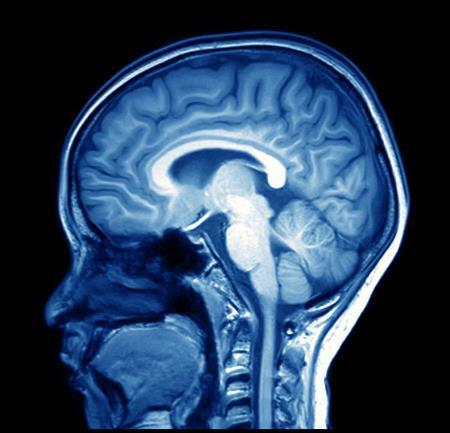

Brain Scans

MRI of the brain can be useful in evaluating problems such as persistent headaches, dizziness, weakness, and blurry vision or seizures, and it can help to detect certain chronic diseases of the nervous system, such as multiple sclerosis. The arteries of the brain can be evaluated non invasively to exclude aneurysms or vascular malformities.